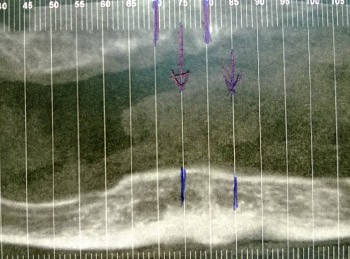

Article réservé à nos abonnés Instruments de préparation canalaire F360® et F6 SkyTaper® répondent-ils à nos attentes ?

Dans le concept F360®, les instruments présentent une conicité de 4 % constante avec des diamètres de pointe de 25, 35,...